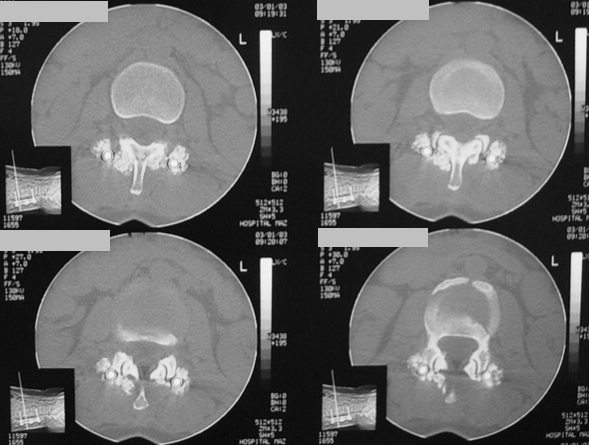

Imagen 4. TC de una artrodesis transpedicular con injerto de AGF obtenido a los 11 meses de la intervencion. Puede verse como la formacion de hueso envuelve literalmente las barras de la artrodesis, solidarizandose con el hueso vertebral.

Imagen 4.